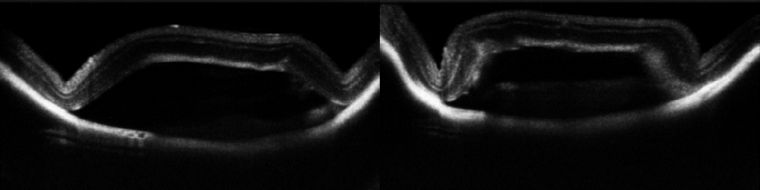

视网膜、角膜OCT断层图-?可定量分枏/strong>

老鼠角膜形态结构变匕/strong>

研究角膜新生血管、碱烧伤方向